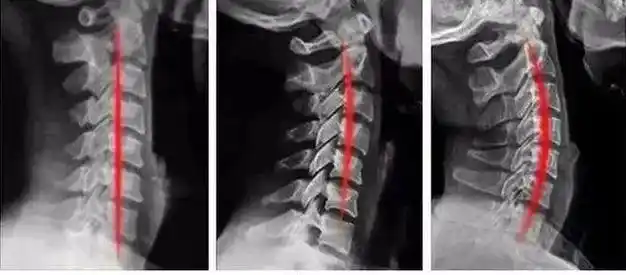

原创脖子越直越可能得颈椎病!医生:颈椎还是弯点儿好

查出颈椎曲度反曲还不注意小心进一步发展为严重颈椎病

经常脖子痛,你的颈椎可能变直了!(了解颈椎的生理曲度)